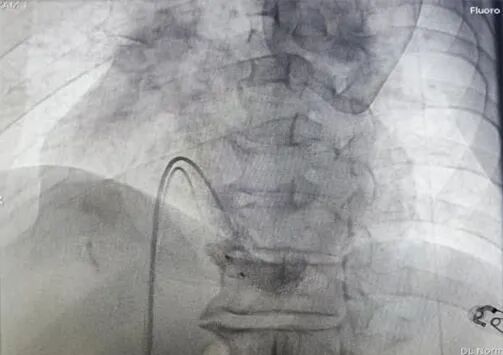

手术过程部分展示

猪尾造影,明确右室心尖、前室间沟、后室间沟、三尖瓣相对位置